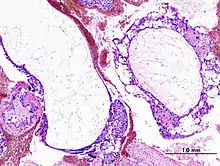

Histopathologic image of hydatidiform mole (complete type). H&E stain.

A hydatidiform mole is a pregnancy/conceptus in which the placenta contains grapelike vesicles (small sacs) that are usually visible to the naked eye. The vesicles arise by distention of the chorionic villi by fluid. When inspected under the microscope, hyperplasia of the trophoblastic tissue is noted. If left untreated, a hydatidiform mole will almost always end as a spontaneous abortion (miscarriage).

Based on morphology, hydatidiform moles can be divided into two types: in complete moles, all the chorionic villi are vesicular, and no sign of embryonic or fetal development is present. In partial moles some villi are vesicular, whereas others appear more normal, and embryonic/fetal development may be seen but the fetus is always malformed and is never viable.